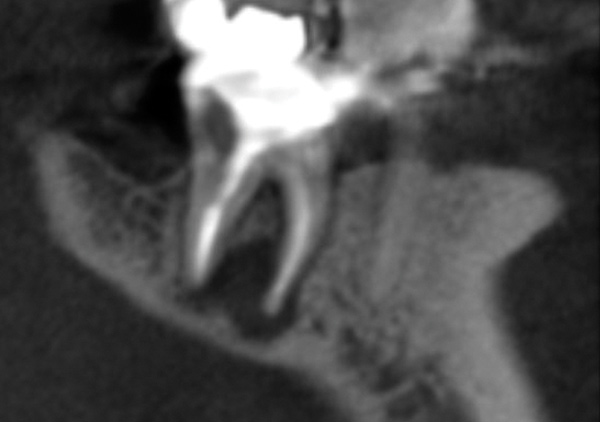

The patient stated that a previous root canal had been performed on tooth No. 18 many years ago, but he had no memory of the exact date or the name of the dentist who provided the treatment. The referring dentist had no records or preoperative radiographs of tooth No. 18 from before the initial endodontic treatment. A limited FOV CBCT scan of the tooth was taken, and a radiolucency was observed on the mesial and distal roots (Figure 4). The pretreatment pulpal diagnosis was "previously treated," and the periradicular diagnosis was symptomatic apical periodontitis.

The clinician determined that the treatment options were conventional endodontic retreatment or endodontic surgery, which would involve resectioning of the mesial and distal roots, preparation of the root ends, and placement of a bioceramic root-end filling. With regard to restorative evaluation, the existing crown on tooth No. 18 was deemed to be within normal limits. Although the periapical radiograph (Figure 3) showed a radiolucent line around the distal portion of the crown, the marginal integrity was determined to be clinically acceptable. The CBCT demonstrated that the inferior alveolar nerve canal was close in proximity to the mesial and distal roots of tooth No. 18. Also, clinically the surgical access around tooth No. 18 was limited for root-end resection endodontic surgery. The axial CBCT view showed that the current canal obturation was within normal limits (Figure 5).

CBCT sagittal view (lingual view exposure) of tooth N o. 18 revealed mesial

and distal root periapical radiolucency.

Fig 4.

CBCT axial view of tooth

No. 18 revealed canal obturation within normal limits.

Fig 5.